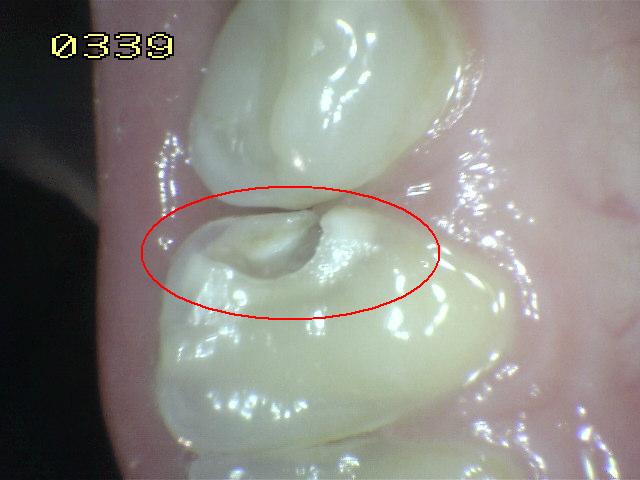

Código 3

(Caries Moderada): Ruptura

localizada del esmalte debido a caries sin dentina visible.

-

La superficie seca muestra una perdida detectable de la

estructura del esmalte. El diente visto en estado

húmedo pueden tener una clara opacidad de caries (mancha blanca

/ marrón)

Una

sonda paeriodontal puede deslizarse sobre la

lesión para comprobar micro-cavidad (pérdida de la

integridad de la superficie de esmalte < 0,5 mm.)